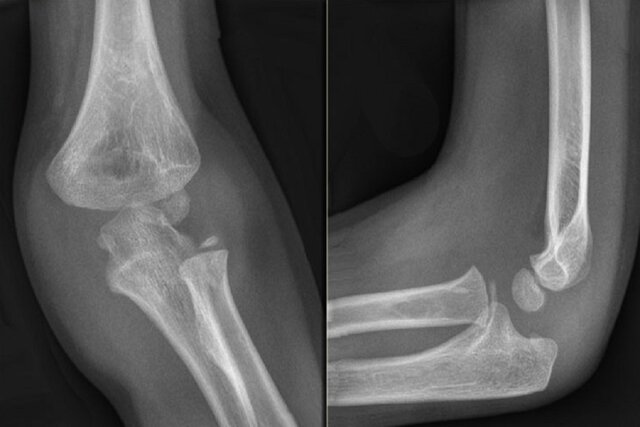

به گزارش بهداشت نیوز، پوکی استخوان یک بیماری نامرئی بوده و تا زمانی که یک استخوان نشکند، علامتی از خود بروز نمی‌دهد. در فرد مبتلا به این بیماری، یک سقوط ساده از ارتفاع کم، یک چرخش ناگهانی، خم و راست شدن سریع یا حتی افتادن در یک چاله کوچک می‌تواند باعث شکستگی استخوان شود. باید توجه کرد که بیشترین شکستگی‌های مربوط به پوکی استخوان، در ناحیه لگن، ستون مهره‌ها، مچ یا قسمت بالای بازو رخ می‌دهد. در دنیا در افراد بالای ۵۰ سال، از هر سه زن یک نفر و از هر پنج مرد یک نفر به این بیماری مبتلا هستند.